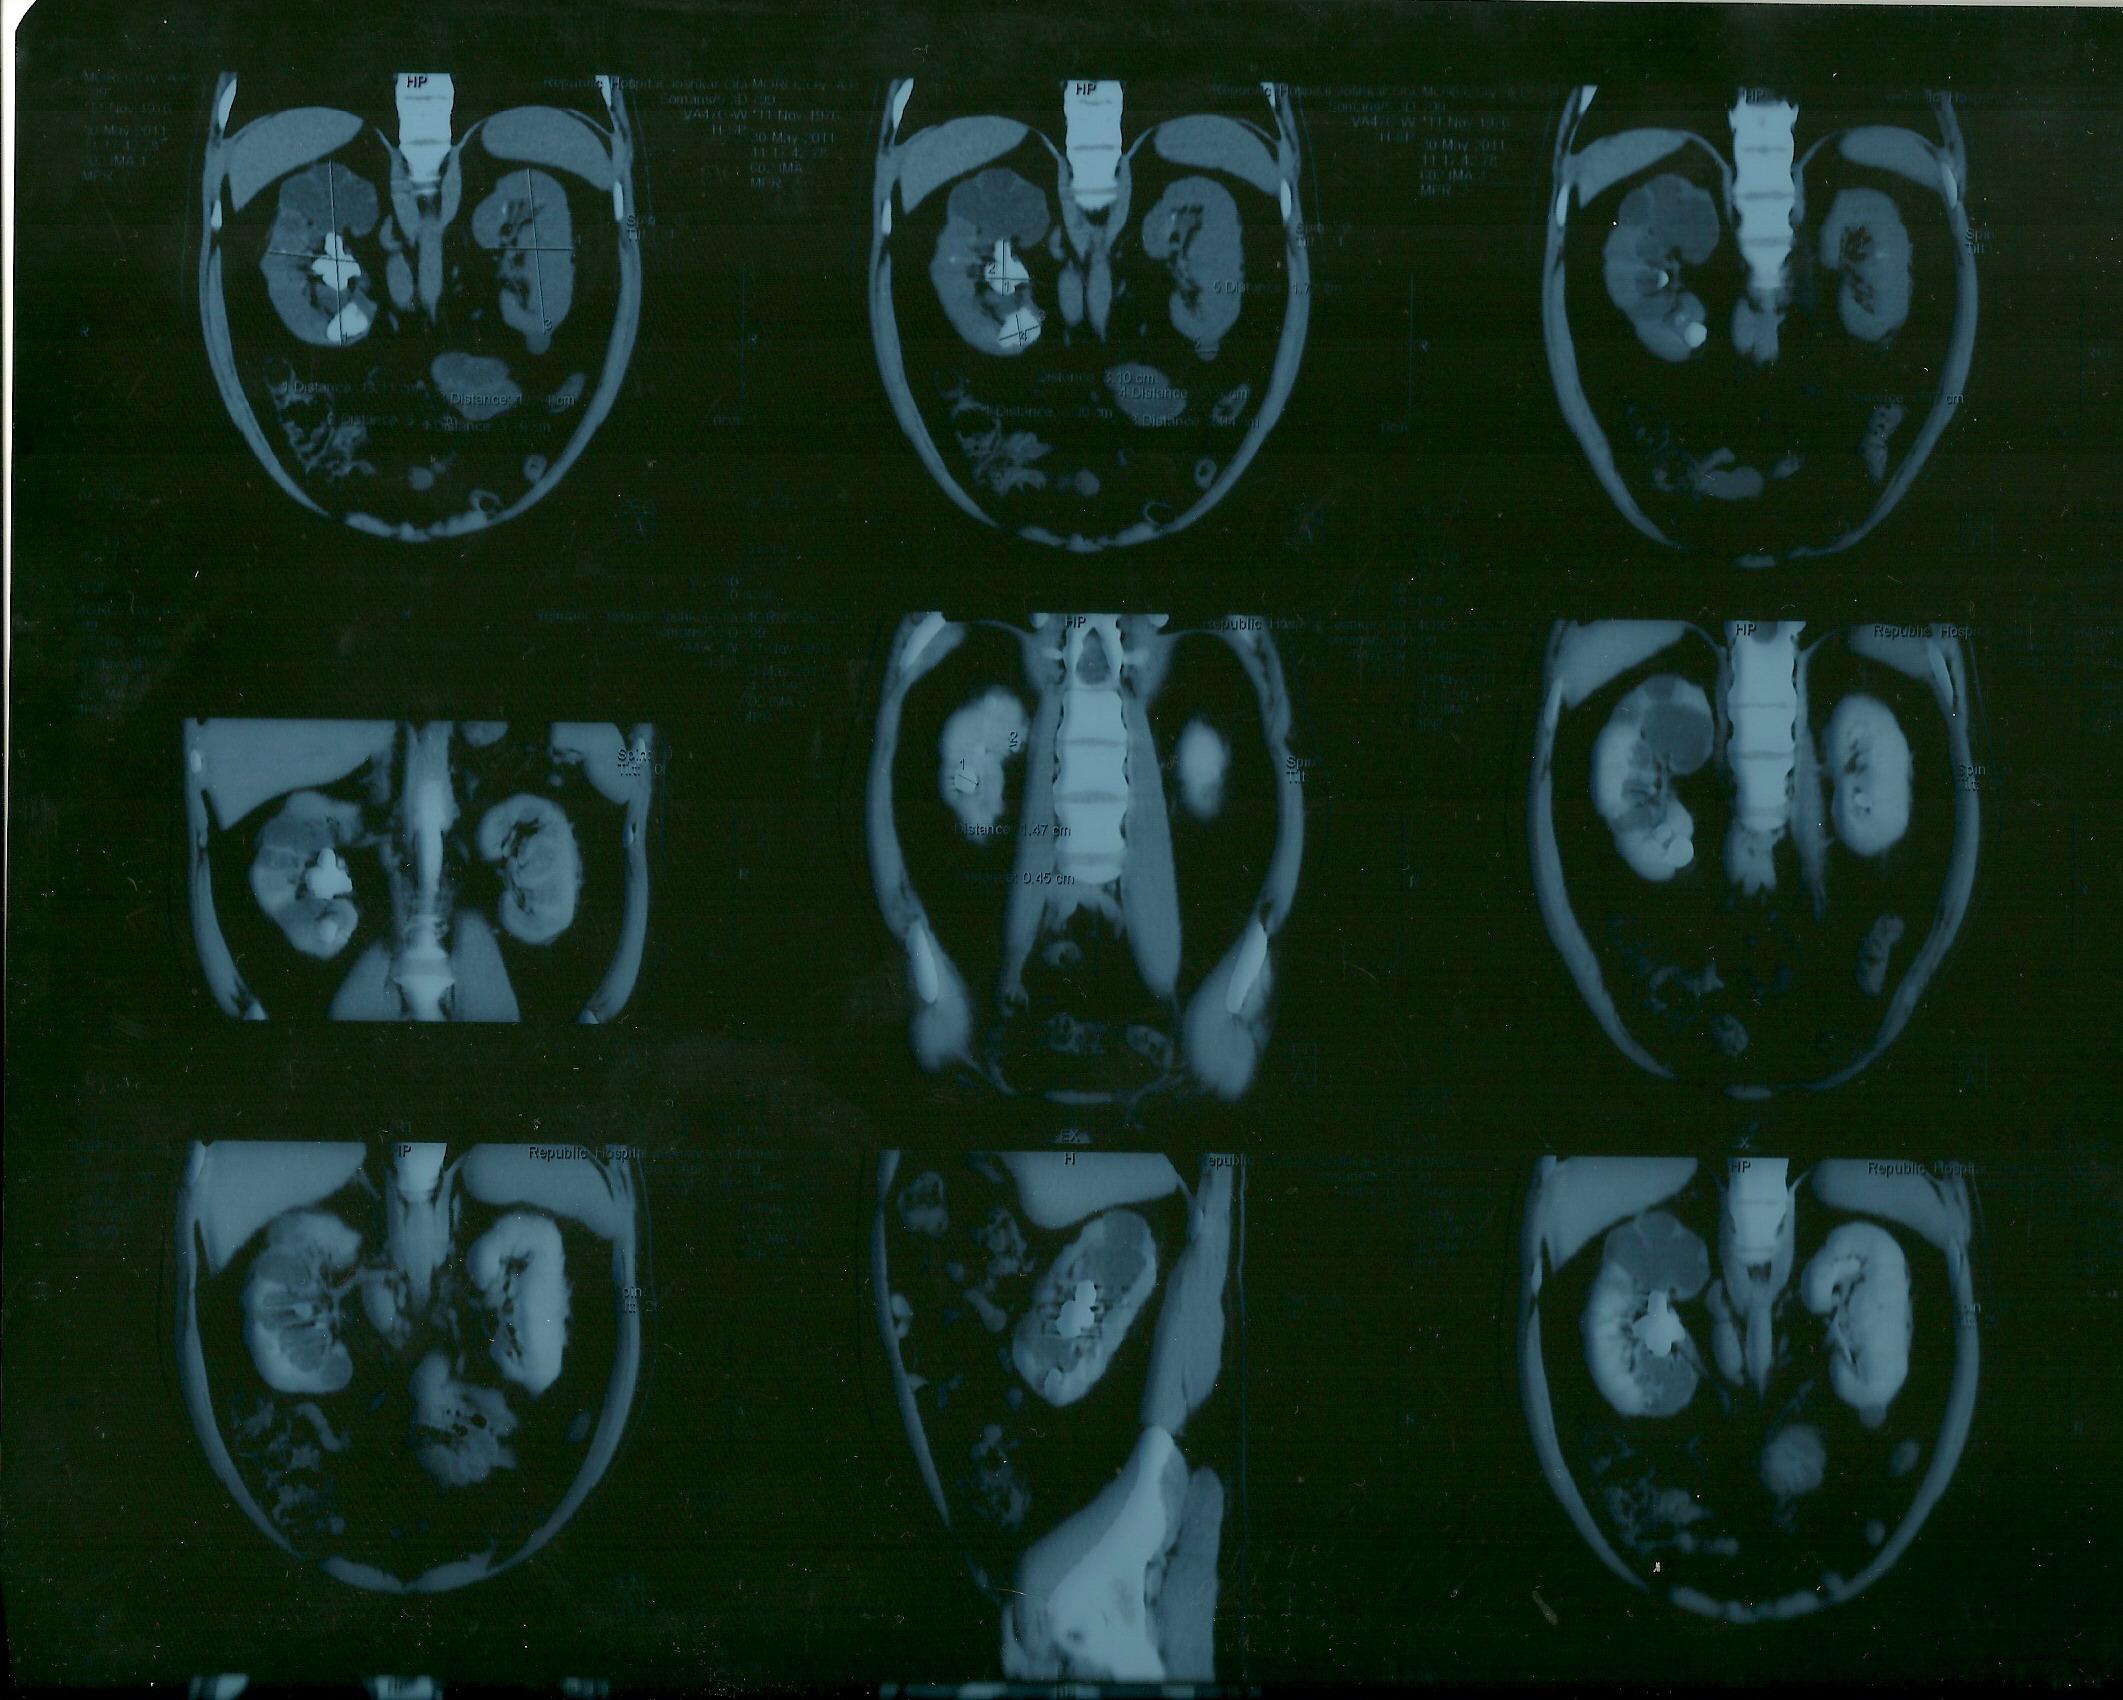

Морозов Алексей. Здравствуйте,находился

на лечении в урологическом отделении

г.Йошкар-Ола по поводу МКБ, В правой почке

обнаружен коралловидный камень,врач

рекомендовал ЧПНЛ в Нижнем Новгороде,но

дело в том что у меня гемофилия,возможно

ли провести данную операцию?

Вы можете прислать мне в почту результаты Ваших обследований